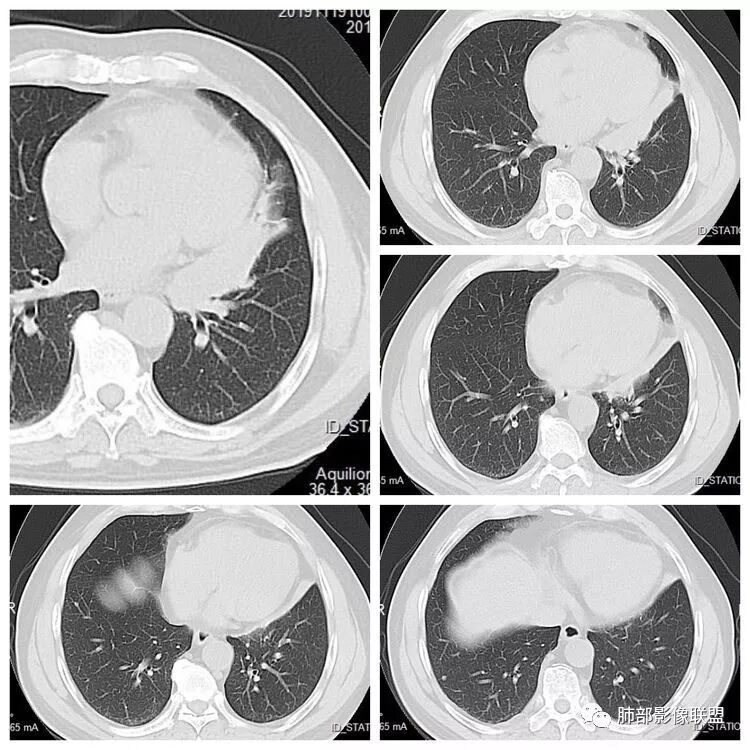

患者,男 ,66岁, “左肺占位”收住院。CEA   5.23 轻度增高

平扫 动脉期 静脉期  40HU、48HU、57HU

患者老年男性,“左肺占位”收入住院。查CEA轻度升高。胸部CT:左肺肺门占位并左肺下叶阻塞性,远端肺组织膨胀不全,增强可见轻度强化,内似见低密度灶。双肺多发类圆形结节,以左肺上叶尖后段为大,内可见部分钙化,边缘光滑、清楚。综合考虑恶性病变,鳞癌并转移可能大,鉴别腺癌、结核。

胸CT:左下叶内前基底段肿块,支气管堵塞,强化弱,延迟强化,两肺多处结节,右上肺门淋巴结大。常规考虑:肺癌可能 ,肺内小结节,转移?鉴别:错构瘤,TB等。

左肺下叶占位,左肺下叶前内支气管阻塞可疑(缺乏薄层),病灶有膨胀性,远端较内侧细,增强病灶强化不明显——乏血供病灶,病灶沿支气管生长,考虑恶性病变,左肺上叶可见小结节病灶,边缘光滑清晰,考虑转移瘤,综上所述考虑恶性病变,左肺下叶小细胞类癌可能,左肺上叶转移。

左上肺光滑圆形结节,内有钙化,密度不均,错构瘤;

左肺下叶结节支气管进入截断,远端肺不张,增强后坏死不均匀,肺癌明显,至于病理类型,鳞癌,小细胞,腺癌都有支持和不支持的地方,个人倾向于鳞癌可能,理由,纵隔淋巴结肿大不明显,远端阻塞性不张,支持小细胞的地方,坏死呈沼泽样,但纵隔无明显淋巴结肿大及冰冻表现。腺癌这种表现一般为低分化腺癌,但远端阻塞性不张及纵隔无明显淋巴结肿大不支持。

1.定位:左肺块影同时累及下舌段及下叶内基底段且相互延续。病灶跨叶,或存在叶裂发育异常,或者说就是病灶的肺门蔓延。

2.病灶前上部分与舌段支气管相关且形成阻塞。

3.左肺上叶另见孤立结节影,边界清楚光整,中央钙化,未见脂质密度特征。

4.增强扫描左肺门区块影轻度强化,强化程度轻于舌段周围不张肺组织。

左肺上叶孤立小结节影未见异常强化。

6.分析:男性患者,左肺门区块状影,支气管阻塞,强化不显著,未见淋巴结肿大,更多见于肺鳞癌。难以解释的是下肺病灶的生长方式。

沿肺门或是叶裂缺损孤立发生且蔓延,转移性腺癌似乎可以解释,但占据较大支气管腔就属罕见了。